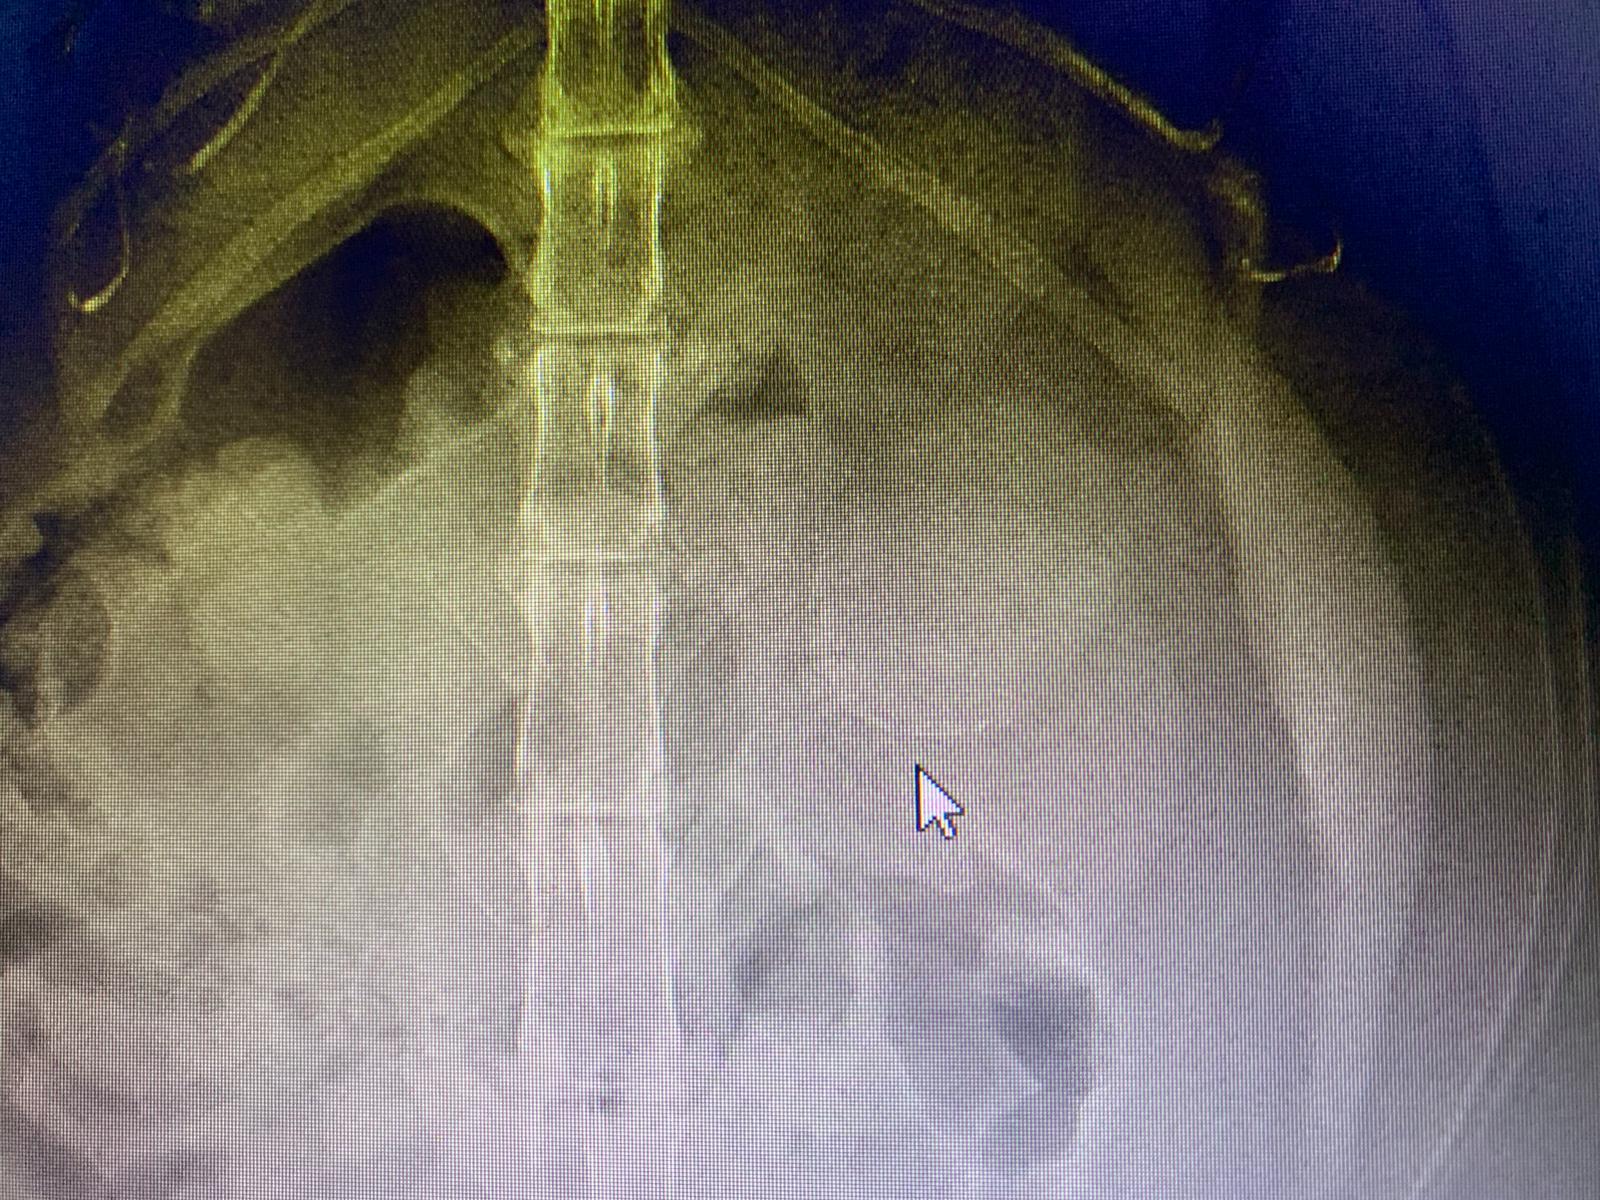

Dr nally says don’t like the muffed sound of his lung, noisy, i scare got fluid ah. Taken X-ray.

X-ray show he got one lump of fluid on the left, cannot confirm what it is. Unless abdominal u/s – I rather spend money on bupre.

His lower spine one part should be in pain.